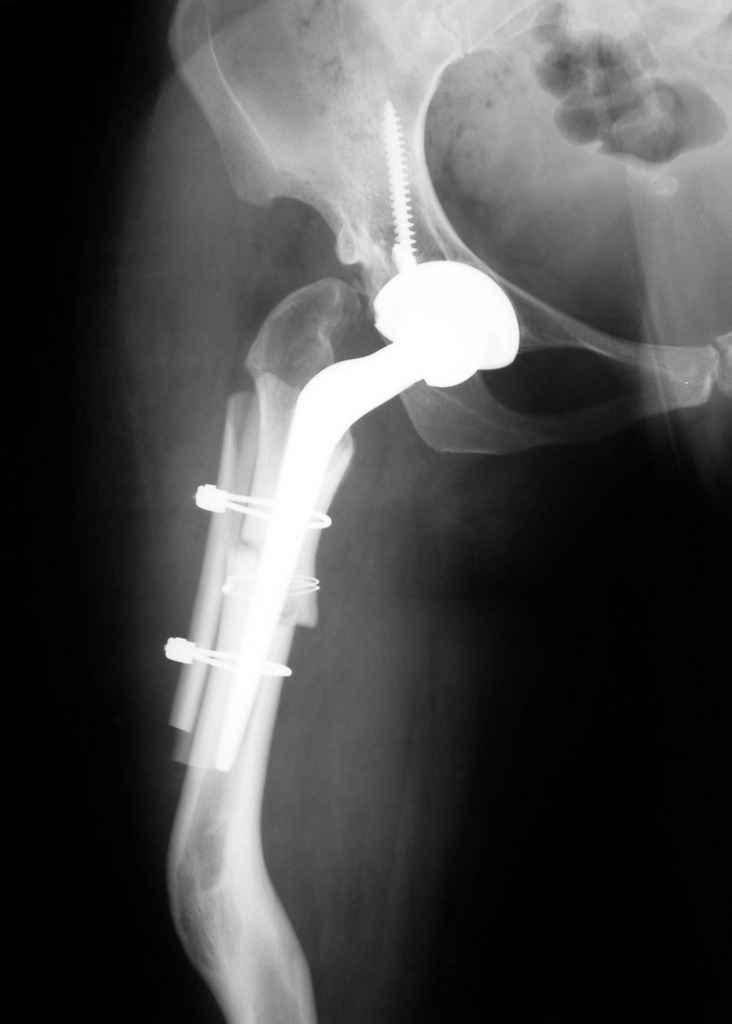

Moghno i tak kak sdelali my: pelvic support + tibial and equinus correction .

Слайд 1

Слайд 2

Слайд 3

Слайд 4

Devushka predstavlennaya na snimke nachala s LLD 9 cm, valgus deformation of the tibia, huge Trendelenburg( vidno na snimke).

Seichas : no LLD ,no Trendelenburg, reasonable hip motion.A samoe glavnoe ei ne predstoit kaghdye 10-15 let delat revision THR.